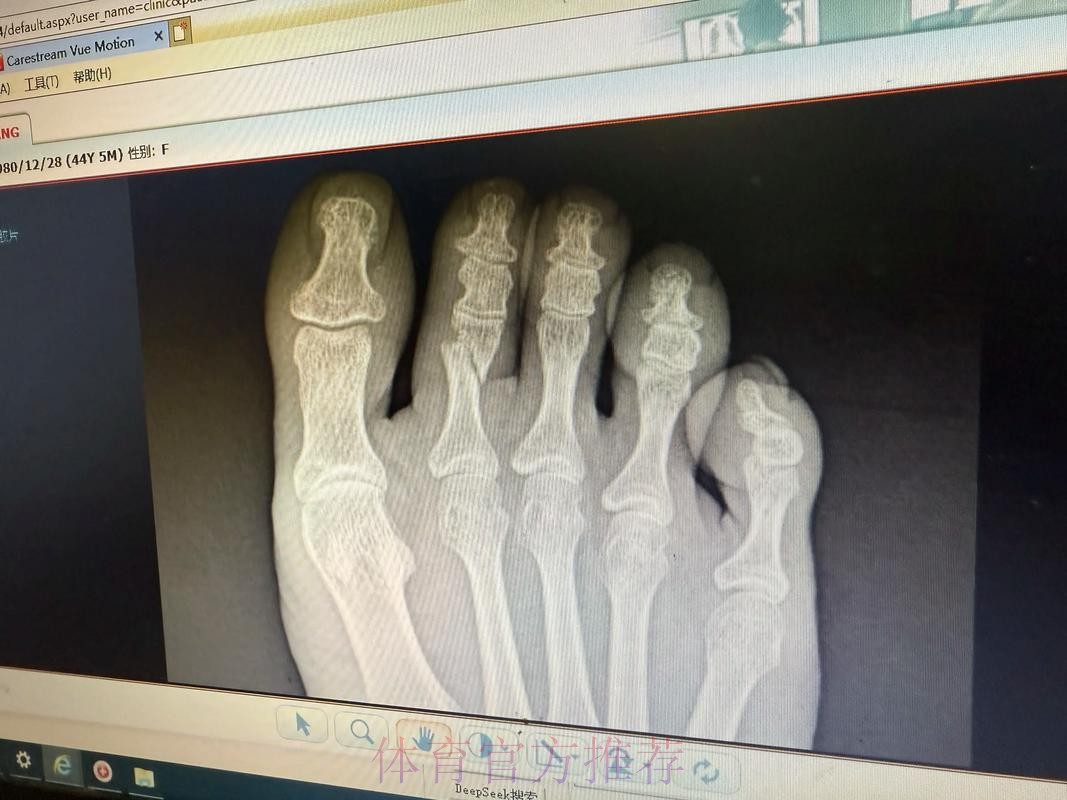

在马德里球迷刚刚享受完一场胜利的余温时,一纸伤病通告突然将伯纳乌的气氛按下了静音键——皇马官方确认,法国中场核心琼阿梅尼左脚第二跖骨出现不完全应力性骨折。这条简短却分量十足的消息,不仅牵动着皇家马德里本赛季的布局,也再一次将高强度现代足球与运动损伤之间的微妙关系推到聚光灯下。对于一支志在联赛欧冠双线冲击的豪门而言,这类伤情远不止是“几周无法出场”那么简单,而是牵连战术、人员、节奏乃至更衣室心理的一连串连锁反应。

皇马官方伤情通告背后的信号 皇马官方一向在伤病信息上措辞谨慎,但“左脚第二跖骨不完全应力性骨折”这句话本身已经透露出不少关键信息。这是跖骨部位的应力性损伤,而非一次剧烈对抗造成的瞬间骨折,说明问题来自长期负荷积累,是典型的疲劳型伤病。“不完全”意味着骨结构尚未完全断裂,仍保持一定连续性,这对康复时间和方式具有决定性影响。如果处理得当,往往可以通过相对保守的治疗方案避免手术;但一旦急于复出或训练负荷控制不当,就有可能从“不完全”演变为完全性骨折,令缺阵期成倍延长。对于依赖琼阿梅尼在中场完成覆盖和防守平衡的皇家马德里来说,如何在争冠压力下保护好球员、又不让球队竞技水准大幅下滑,将是一场同样艰难的“心理博弈”。

跖骨应力性骨折究竟意味着什么 许多球迷听到“应力性骨折”会下意识以为只是轻微小伤,但在运动医学语境中,这却是对高负荷训练的一种严肃警告。跖骨是足部承重和发力的重要骨骼,足球运动中的短距离爆发、急停变向、频繁起跳落地,都会不断将力量传导至跖骨区域。当训练和比赛的总量超过身体适应阈值,同时恢复时间又不足时,骨组织内部会出现微小裂纹,这些微裂如果得不到及时修复,就逐渐累积形成应力性骨折。不完全应力性骨折通常意味着裂纹尚未贯通骨骼,两侧仍存在结构支撑,因此患者在早期往往还能咬牙坚持训练甚至上场。但正是这种“还能坚持”的错觉,使得应力性骨折在职业足球中极具隐蔽性——当你真正感觉到强烈疼痛时,很可能已经接近完全骨折的边缘。琼阿梅尼的伤情被及时查出,某种程度上说明皇马医疗团队对他的反馈足够重视,也体现了俱乐部在数据监控和身体管理上的专业度。

琼阿梅尼角色特殊性与风险叠加 和普通中场球员相比,琼阿梅尼在皇马体系中的角色决定了他更容易接触到伤病“红线”。作为防守型中场,他既要承担大范围横向覆盖,又要参与由守转攻时的向前推动,跑动距离大、对抗频率高、折返次数密集,这些特点意味着足部负荷远高于普通位置。皇马本赛季在多线作战中经常需要他“连轴转”,特别是在一些关键焦点战役里,他几乎难以得到轮换休息的空间。高强度节奏、稀缺替代者、持续高压环境三者叠加,很容易将隐性疲劳推向临界点。当官方通告确认为左脚第二跖骨不完全应力性骨折时,其实也在提醒人们:在强调胜利和冠军的职业环境下,如何为核心球员建立更科学的负荷管理模型,将直接影响球队的长期竞争力,而不只是某一场比赛的结果。

运动医学视角下的康复和复出节奏 从医学角度看,左脚第二跖骨不完全应力性骨折的康复核心在于“控制负荷”和“逐步恢复”。初期需要通过休息和减压让骨组织完成自我修复,有时会配合使用护靴或拐杖减少足部承重;中期则通过理疗、轻量力量训练和本体感觉训练逐步恢复功能;后期则要加入跑动、变向和带球训练,模拟比赛中的真实对抗场景。真正的难点不在诊断,而在“何时可以回到90分钟高强度比赛”这道关卡。如果皇马在赛程压力或舆论压力下过早安排琼阿梅尼复出,哪怕他在短时间内状态看似良好,也可能埋下复发或二次伤病的隐患。对球员而言,学会倾听身体信号,与医疗团队保持坦诚沟通,避免“硬扛文化”的主导,也是职业生涯能否拉长的重要因素。

多线作战时代的隐形代价 皇马官方关于这次伤情的公告,其实折射出整个欧洲豪门共同面临的现实——赛程越来越密集,商业比赛与国家队任务不断叠加,球员身体被高度透支。以琼阿梅尼为例,他既是俱乐部的重要一员,也是法国国家队的中场支柱,国际比赛日往往意味着长途奔波和高压对抗。即便训练负荷控制得再精细,也很难完全抵消比赛本身带来的累积应力。当类似“左脚第二跖骨不完全应力性骨折”这样的伤病频繁出现在新闻标题中时,实际上是整个行业在为高密度赛制埋单。如何通过更合理的赛历安排、更加精细的轮换机制以及更先进的恢复手段,避免将球员推向身体极限,将决定未来职业足球是否能在观赏性与可持续性之间找到平衡点。